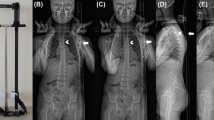

From the downloaded image files, vertebral angles (relative to the computer's X-axis) from each of the 5 individual vertebral markings of the human subject sequences were all plotted throughout the motion. An example of this is shown (Figure 6). All the graphs start off from zero and because the template assigned to the first image is used throughout the sequence, the results are independent of which vertebral landmarks are chosen to define this template in the first instance.

Only graphs in which all vertebral angles in the 5 runs coincided visually were regarded as reliable and therefore entered into the data pool. Two observers independently inspected all graphs for inclusion. Only those that met this criterion and were adjacent to vertebrae whose graphs did too, were analysed. The analysis consisted of subtracting the vertebral angle sequences of adjacent segments from each other in all combinations (i.e. L1a-L2a, L1a-L2b, L1b-L2b etc) to give inter-vertebral angles throughout the motion. This gave 25 individual inter-vertebral angles for each of 120 images in each motion sequence. These were represented graphically with the median as a solid line and each of the individual 25 points as a scatter plot (Figure 7), showing the full range and variation of each vertebral angle subtraction.

Forty-three motion segments (vertebral pairs) from L3 to L5 could be reliably tracked in side-bending motion for both first and second screenings. These provided inter-vertebral motion graphs from 43 adjacent vertebrae whose individual analyses coincided over 5 separate markings (Figure 6). Figure 8 shows an example of sidebending inter-vertebral motion graphs at the L4-5 level between observers and between screenings.

The motion patterns were all regular and in the direction of trunk motion, but not always symmetrical, as can be seen in Figure 8. The inter-observer variation (RMS) of intervertebral rotational range was 1.86° for side-bending and 1.94° for flexion-extension. The intra-subject biological variation for side-bending range was 2.75° and 2.91° for Observers 1 and 2 respectively (Table 4).